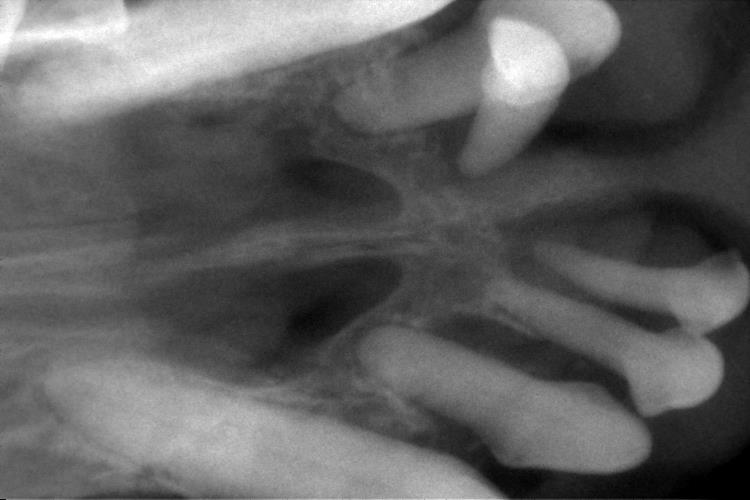

上顎の切歯はすべて歯根の周りが黒く抜け、歯を支えている部分がとても少ないことがわかります。

これらの歯は、歯周病の進行により歯を支えている歯槽骨が吸収され、ぐらついています。